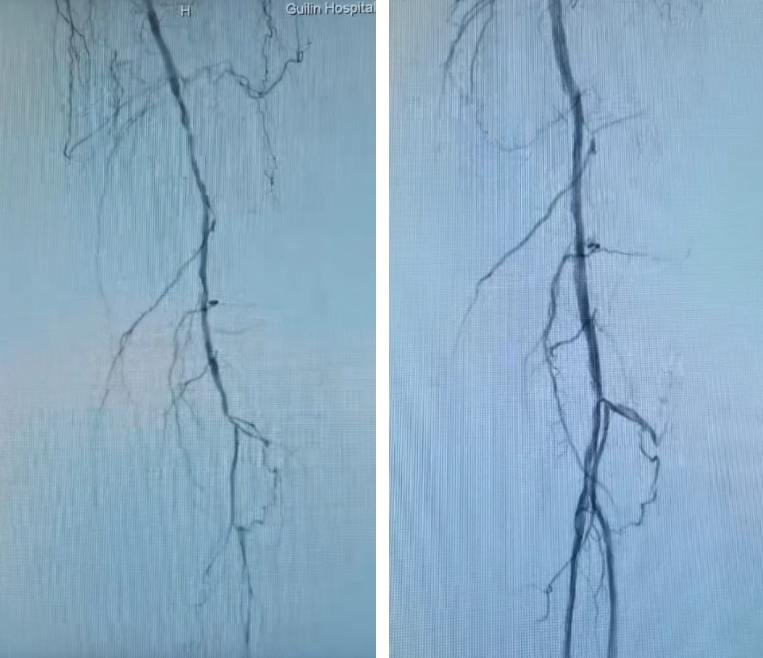

股浅动脉长段闭塞段术前(左)血流中断,术后(右)真腔成功开通